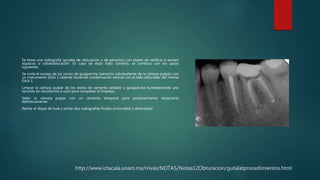

Se toma una radiografía (prueba de obturación o de penacho) con objeto de verificar si existen

espacios o sobreobturación. En caso de estar todo correcto, se continua con los pasos

siguientes.

Se corta el exceso de los conos de gutapercha (penacho sobresaliente de la cámara pulpar) con

un instrumento Glick 1 caliente haciendo condensación vertical con el lado obturador del mismo

Glick 1.

Limpiar la cámara pulpar de los restos de cemento sellador y gutapercha humedeciendo una

torunda en cloroformo o xylol para completar la limpieza.

Sellar la cámara pulpar con un cemento temporal para posteriormente restaurarlo

definitivamente.

Retirar el dique de hule y tomar dos radiografías finales (ortorradial y distoradial)

 Ya realizado el corte de los penachos hasta el cuello de la pieza dental

procedemos a la obturación de la pieza dental y tomamos nuestra ultima

radiografía que nos dirá si el tratamiento fue exitoso.

Buen terminado apical

Terminado cervical

correcto

 Se pide disculpas por el mal estado de las radiografías 